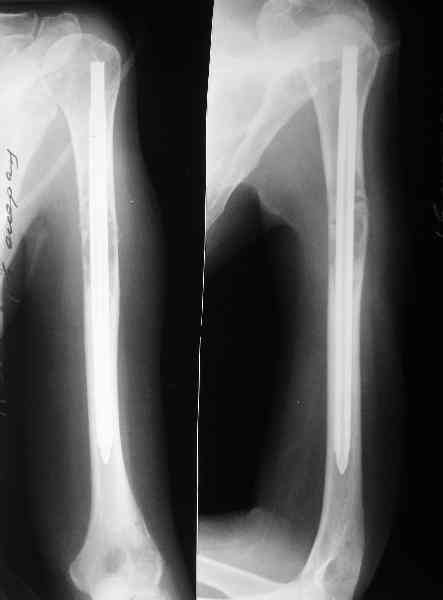

Женщина 53 лет получила патологический перелом правого плеча в феварле, и левого в марте - mts из невыясненного первичного очага.

Онкологи провели облучение, руки на косынки, время от времени наблюдают, вводили зомету.На нас вышли родственники. Состояние пациентки уже не очень, анемия (Hb -50-60 г/л), исхудалв, но асцита нет, в легких чисто. Поскольку женщина совершенно беспомощна, решили сделать остеосиннтез.

Сегодня сделали, Fixion диаметром 7,4 мм. Обе пперации продолжались по 7 мин. Картинки в приложении. Наркоз был диприваном, на спонтанном дыхании. По крайней мере, пока довольны хотя бы анестезиологи, похоже, не верили, что управимся меньше, чем за час ;-)

Гвоздик 7,4 расширяется до 11 мм. Не маловато ли, судя по снимкам?

Обсалютным показанием для использования этого стержня,из моей практики, являетются поперечные переломы диафиза пдечевой и большеберцовой костей.Преимущество его в удобстве репозиции и продалжительности операчии.Недостаток в сдабой ротационной стабильности.Учитывая состояние больной,метод был выбран правильно.Мы этих больных оперируем тогда когда приблизительный срок выживания превышает шесть месяцев и конечно же всотрудничестве с окологами.

7,4 мм, рсширяющийся до 11 мм, в принципе, достаточно для плеча. Хотя мне тоже показалось, что можно было бы и потолще. Вообще есть и следующий диаметр, 8,5 мм, расширяющийся до 13,5 мм, но его в наличии на сегодня не было.